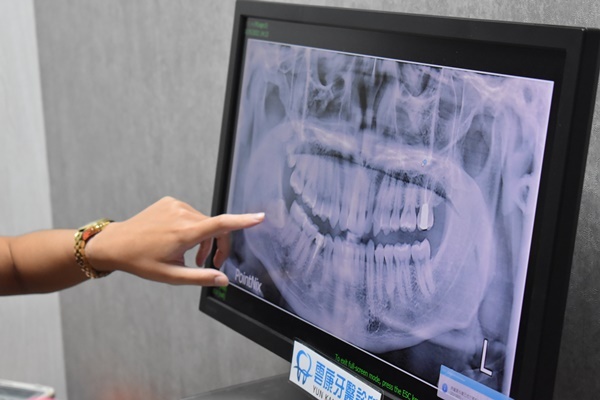

另外,一次植多顆牙齒的風險不見得較高,手術風險反而跟「術前評估」及「醫師經驗」比較相關。術前必須謹慎評估病人有無糖尿病、高血壓或血友病,才能降低手術出血及術後感染的風險,若是醫師經驗不夠豐富,即使只有植一顆,但這顆牙若掉到上顎竇或壓迫神經,恐怕都會帶來其他後遺症,所以想要植牙成功,術前評估和慎選醫師才能增加多顆植牙安全性,所以寧可多花一點植牙價錢找足以信賴的植牙權威醫師來減少手術風險。

手術前先到診所做斷層掃描和諮詢,媽媽因為長期缺牙,骨質與骨量不佳,所以要先補骨粉。雲康牙醫可以線上預約,回覆的速度也很快,約診前一天時小護士都會非常貼心的傳送訊息提醒預約時間,揪甘心ㄟ!